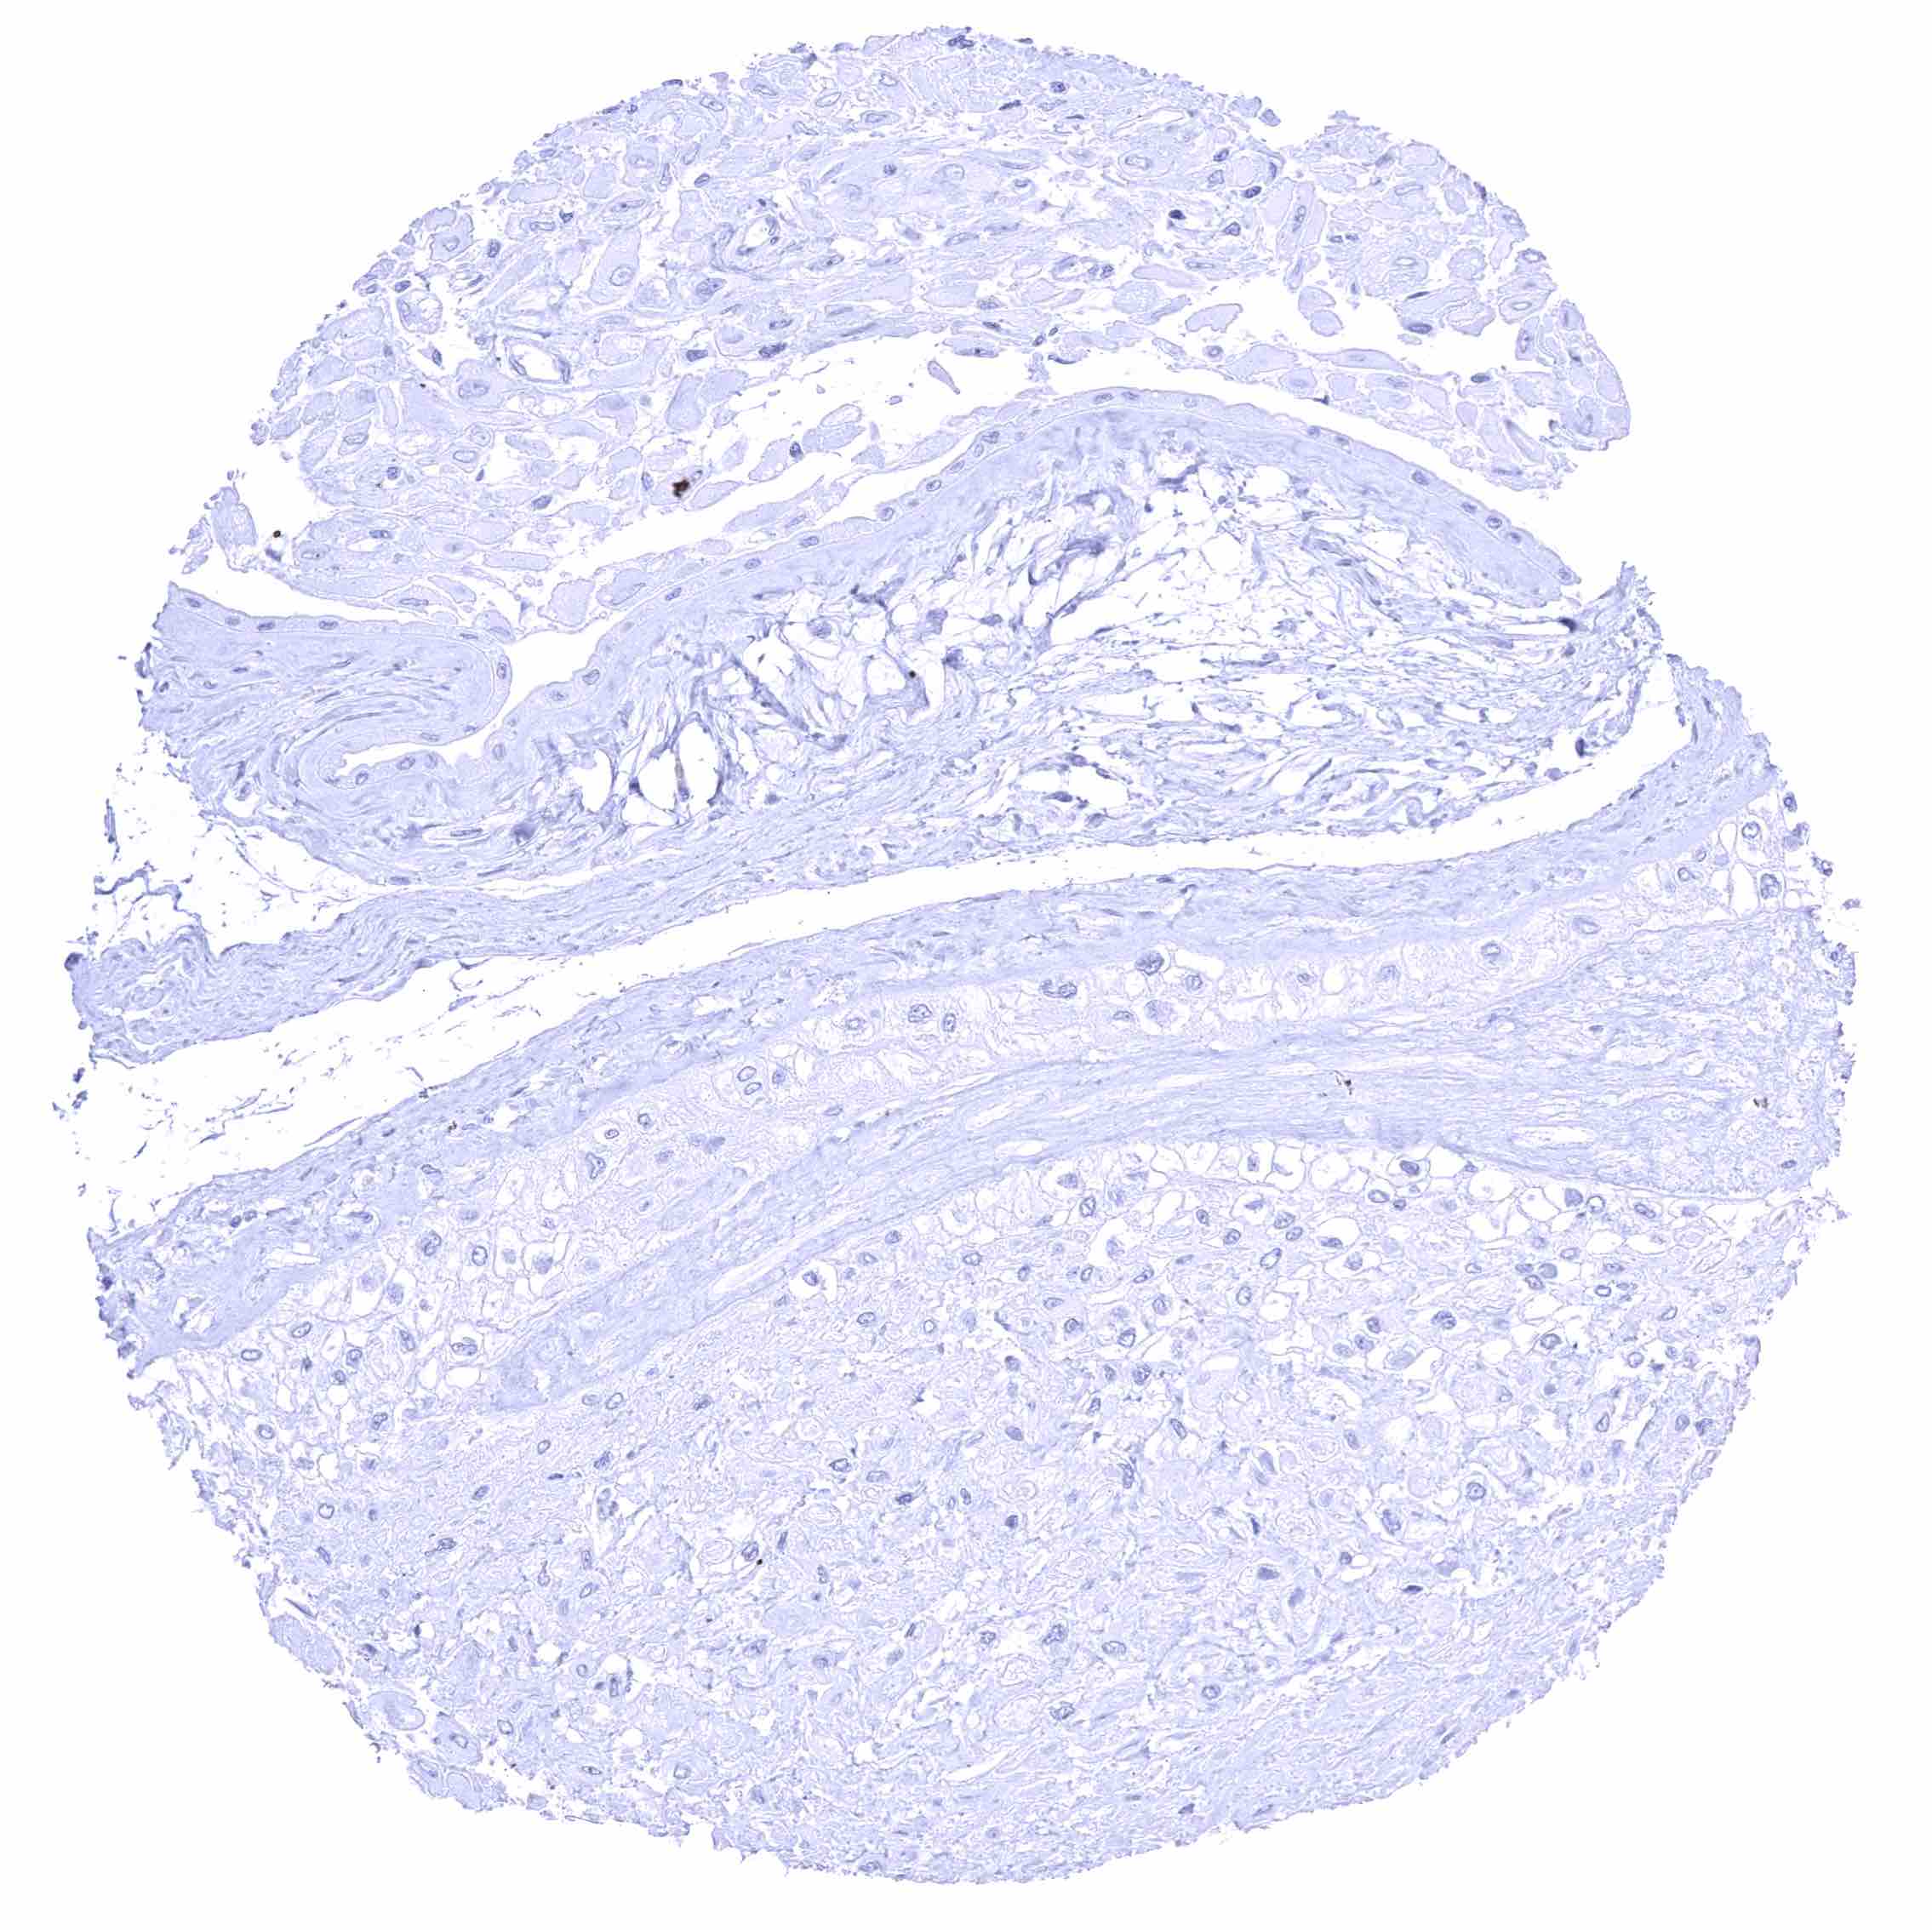

Esophagus, muscular wall

Esophagus, squamous epithelium